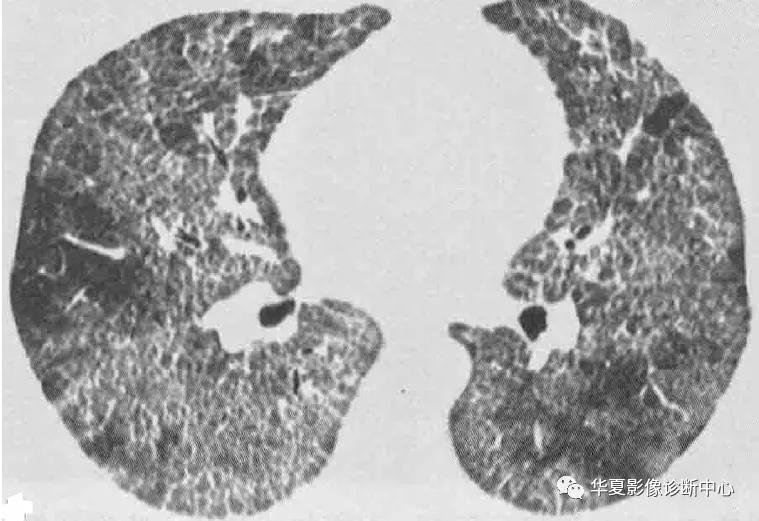

影像学表现:X线特征性表现为爽哦片状实变内隐约可见结节,50%病例实变分布于肺门周围,其余病例随机分布或主要分布于周边或基底部,有时肺实质受累不对称或单侧受累。CT主要典型表现为双侧磨玻璃影(尤其肺背侧部分),几乎均匀累及全非,也可以下肺分布为主,大部分病例可见碎石铺路征,即一个细线形成的直径3-10mm多边形叠加在磨玻璃影上,反应了肺间质水肿的存在或小叶间隔毗邻的空腔内脂蛋白样物质的聚集;正常和异常肺实质边界锐利清楚。